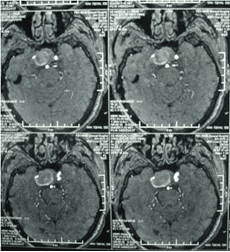

經(jīng)顱多普勒

頸內(nèi)動脈虹吸段巨大動脈瘤(約3cm ×3cm

顱內(nèi)動脈瘤是指腦動脈的局部性異常擴(kuò)大,多在腦底動脈的分叉處或分支的夾角向外突出,多呈囊狀。TCD對顱內(nèi)動脈瘤的總檢出率為67 %,動脈瘤>1cm的檢出率為82 %。TC D 對較大動脈瘤的檢測有其特征性表現(xiàn),其典型表現(xiàn)為:瘤體內(nèi)血流速度明顯低于載瘤動脈血流速度,其收縮峰陡峭或多峰不整,舒張期末流速極低或斷流,PI 值增高,多為雙向血流,聲頻低鈍,似撞擊樣轟鳴音。